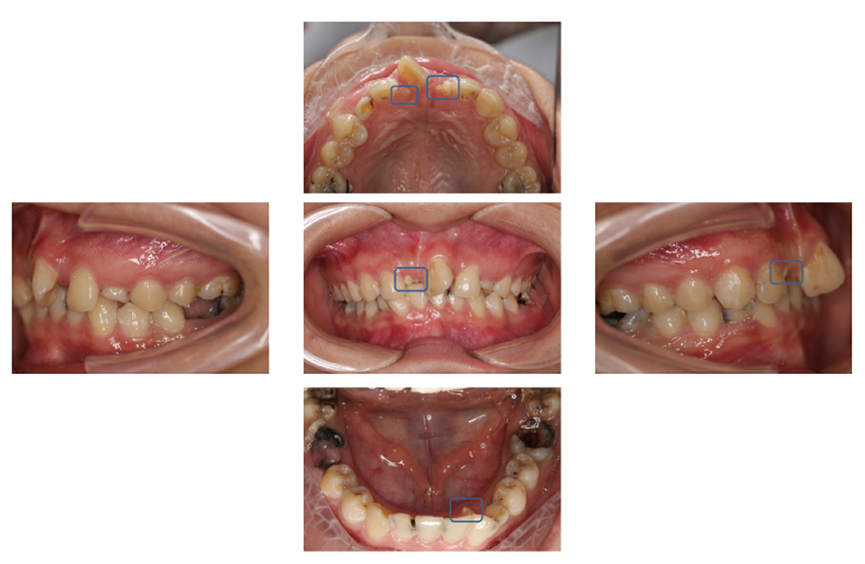

深圳市民杨女士总觉得自己的牙齿不整齐,每次照镜子,还不时看到几颗小“尖牙”露在外面,特别闹心。

右侧的门牙完全阻生,长在鼻子底下,一颗米粒大的多生牙“鸠占鹊巢”,占了原本门牙的位置;

在儿童青少年时期,多生牙常可引起恒牙迟萌或阻生,出现牙间缝隙、邻牙的错位或者扭转,造成牙列不齐,影响正常咀嚼能力,影响牙齿和面部美观。

多生牙挤占了门牙的正常位置,造成牙齿扭转,拔除多生牙后通过正畸矫治成功。(儿童口腔科田雨医生提供)

因多生牙造成的牙列不齐、邻牙错位扭转等情况,可以在拔除多生牙之后,做正畸治疗来进行矫正,以获得满意的效果。